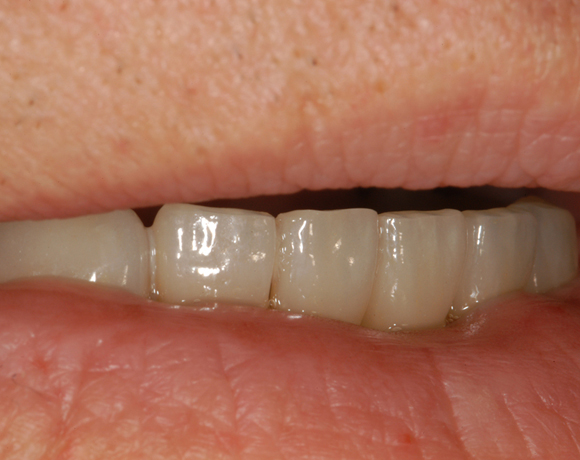

6 Implantate und viele Kronen und Brücken

Mit dem zweiteiligen vollkeramischen Implantat lassen sich auch große Lücken überbrücken.

Ein Projekt aus dem Jahr 2011

Im vorliegenden Patientenfall waren die Zähne 11 – 26 mit einer provisorischen Brücke versorgt, der Patient konnte damit aber nicht essen. Auch im Unterkiefer waren die vorhandenen Kronen und Brücken insuffizient. Es wurde eine komplette Neuversorgung für Ober- wie Unterkiefer geplant.